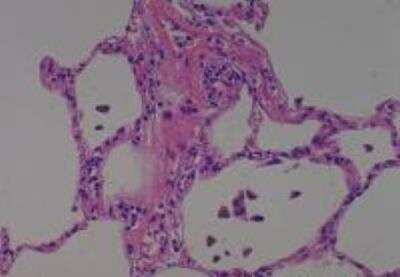

Hematoxylin & Eosin Stain: Human Common Tissue MicroArray (Normal Adjacent) [NBP2-30215] - 103. Stomach